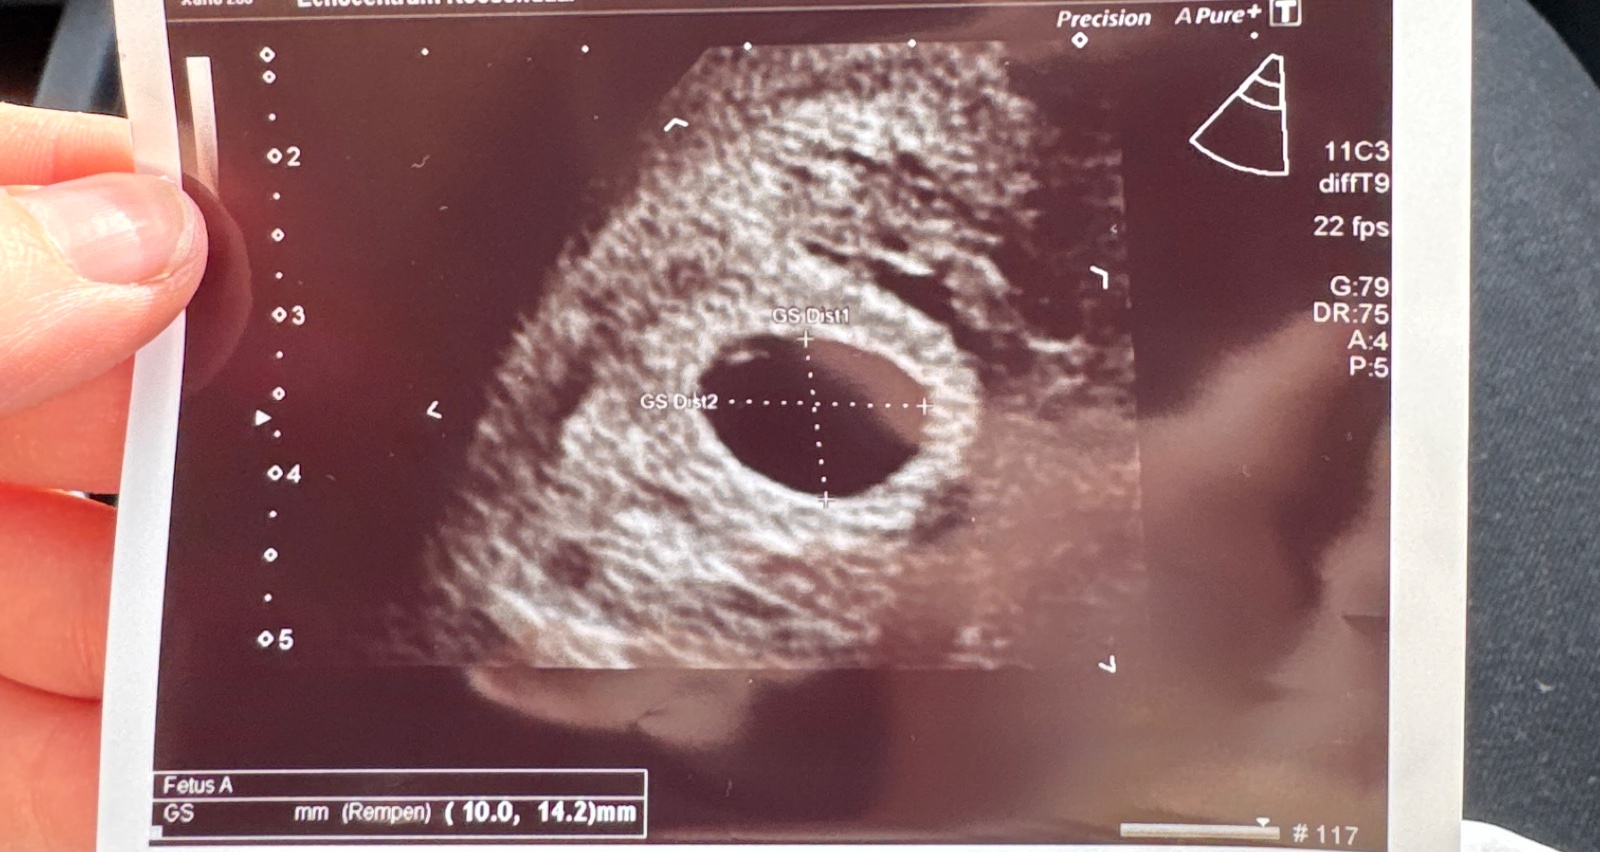

Ahojte, dnes som mala prvý ultrazvuk, to že som tehotná som sa dozvedela pred 21.2., dr ma objednala na dnes, toho 21.2. som si robila aj clearblue digitalny ktory mi pisal 1-2. Poslednú ms som mala 16.1., no ovuláciu som mala posunutú, viem na základe cervikálneho hlienu no neviem presne ktorý deň bola ovulácia, len viem že to bolo niekedy v týždni 3-7.2. cca. No dnes na ultrazvuku bol gestačný vak, ktorý zodpovedal 5tt + nejaké dni, no veľkosť plodu zodpovedala tak 4tt +nejaké dni, ani som si to v tom strese nezapamätala presne. Vraj je veľmi malý na to, v ktorom týždni by som byť mala a neviem teraz, či ta ovulácia bola posunutá nejak viac, o 10dní idem na ďalší ultrazvuk, kde teda budeme vidieť, či plod rastie, alebo nie.. dosť sa bojím a mám z toho stresy, to čakanie je vždy nekonečné, asi len potrebujem počuť, či to má nádej, alebo radšej mám byť stotožnená s tým, že z toho nič nebude, či niekto mal takúto situáciu a nakoniec to dopadlo dobre.. za všetky rady vopred ďakujem.🥹

@sasikes no ona ma objednala na ten prvý ultrazvuk vpodstate na základe poslednej ms lebo podľa ms by som aktuálne mala byť cca v 7týždni, no na 100% viem že ovuláciu som mala neskôr. A tým že teda to veľkostne na ten týždeň vôbec nesedí mi to takto povedala, ja som aj bola dosť v strese + do toho som v zahraničí tak to bolo pre mňa ešte viac stresujúce. Ale teda snáď to bude rásť a bude to okej. Vďaka❤️prikladám aj foto.